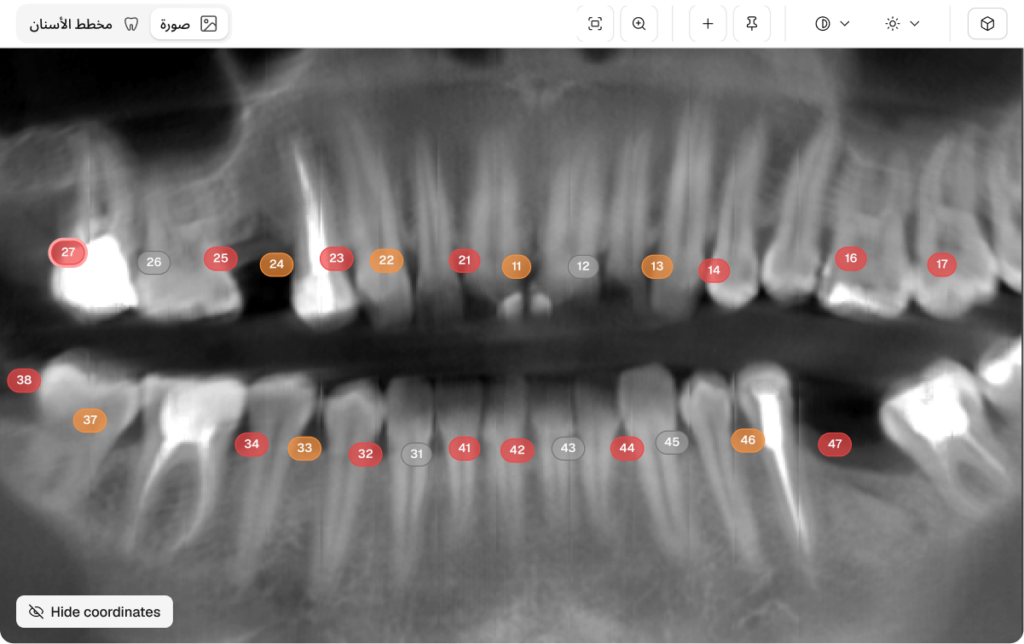

يتم تدريب Dento على قاعدة بيانات شاملة لصور التصوير المقطعي المحوسب (CBCT) ، مع دقة لا مثيل لها في تحديد وتصنيف 10+ أمراض الأسنان الحرجة إلى جانب تحليل شامل لـ 14+ العلاجات السابقة. أحدث إصدار لدينا يتجاوز الاكتشاف البسيط ، ويقدم ملف محرر الإنسان في الحلقة و وحدة الإحصاء مصممة للإدارة السريرية على نطاق المؤسسات. تقدم Dento الآن تحكمًا تشخيصيًا كاملًا ، مما يسمح للأطباء بتحسين نتائج الذكاء الاصطناعي وتتبع الأداء التنظيمي بدقة تعتمد على البيانات.

تتيح قدرة برنامج Dentomo على تحديد أكثر من 10 أمراض فموية وأكثر من 14 علاجًا تلقائيًا، مع ميزة البحث الدقيق حسب الكيان أو العيادة أو المستخدم، رؤية شاملة لصحة فم المريض. تمكّن هذه المعلومات القيّمة الأطباء من اتخاذ قرارات مدروسة، مما يؤدي إلى خطط علاجية أكثر تخصيصًا ومستوى رعاية أعلى.